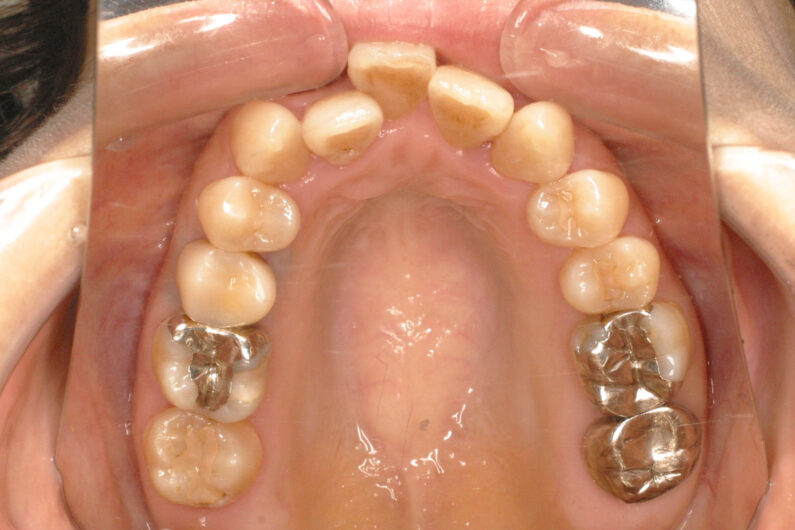

前歯部に叢生(がたつき)がある、受け口、前歯反対咬合の患者さんです。

虫歯の処置歯が多いだけでなく、左上の側切歯が欠如しており、上顎正中(歯並びの中心)が1歯分、左側にずれています。

前歯部の被蓋(咬み合わせ、重なり)と叢生の改善、上顎正中の右側移動を目的として、抜歯による治療を行いました。

マルチブラケット 動的治療期間 2年1か月 調整回数27回